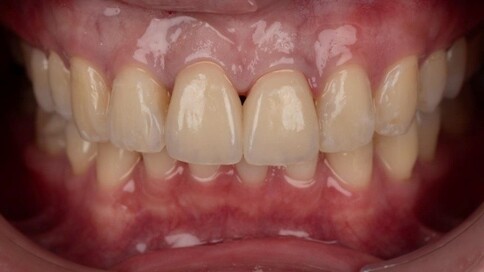

當您只有「單顆」門牙受損時,挑戰在於模仿隔壁那顆「天生的牙」。我們利用全瓷冠的高透光性創造視覺平衡,避免做出一顆看起來很新卻很突兀的假牙。

Case 1:舊假牙死白換新,牙肉回彈跡象。